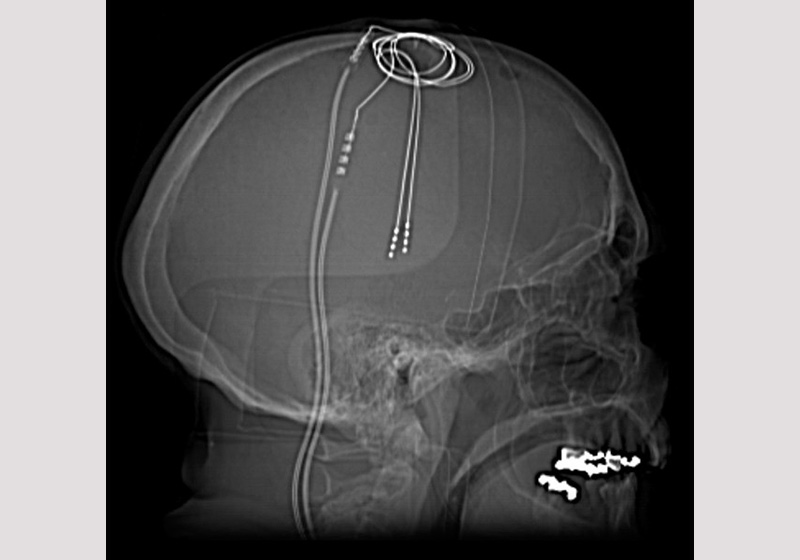

A estimulação cerebral profunda, aprovada pelo FDA, Food and Drug Administration, é um procedimento neurocirúrgico que envolve a colocação de um neuroestimulador – chamado de “marcapasso cerebral” – que envia impulsos elétricos de alta frequência através de eletrodos implantados no fundo do cérebro, em áreas responsáveis pelos sintomas de cada distúrbio.

O estudo documenta os dados de resultados a longo prazo (4 a 8 anos) de 28 pacientes que foram incluídos em um ensaio clínico de rótulo aberto do SCC DBS para depressão resistente ao tratamento.